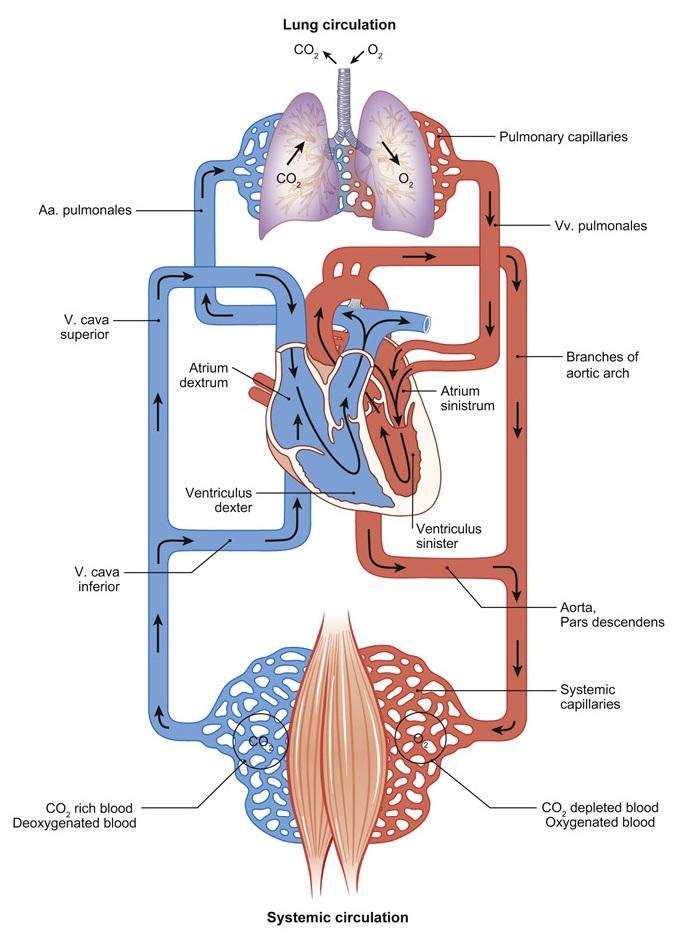

Fig 3.02: Lymfatisch systeem

hydrostatische druk osmotische druk veel vochtverlies t.h.v. capillairen 90% terug opgenomen via bloedvaten overige 10% via Lymfewegen (vasa lymphatica) (ductus lymphaticus)